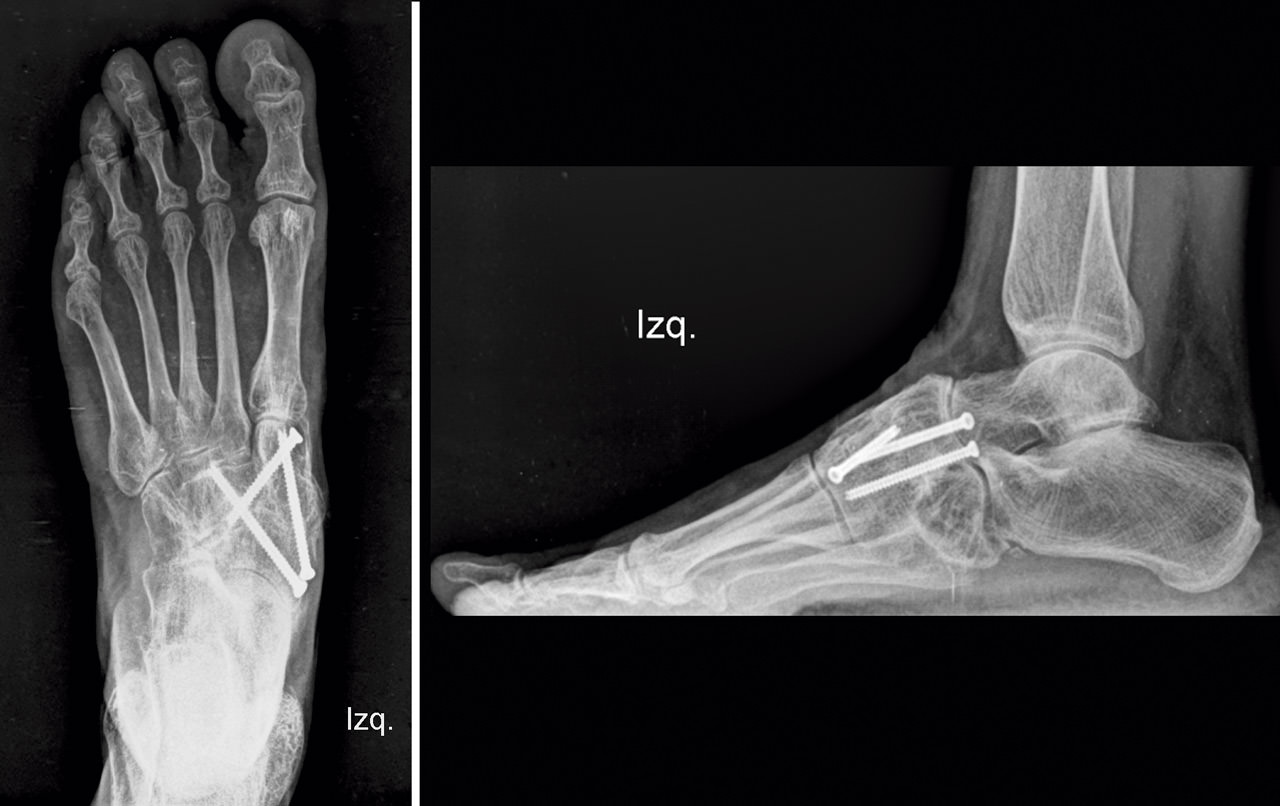

En el postoperatorio, la paciente llevó una inmovilización con férula de yeso las 2 primeras semanas y una bota de yeso durante 4 semanas más. A partir de las 6 semanas se le autorizó la carga con una ortesis de tipo Rom Walker®. A los 3 meses se comprobó la consolidación con el estudio radiológico (Figura 6), retirándose la ortesis, y se inició el tratamiento rehabilitador. Tras un periodo de 8 semanas de tratamiento fisioterápico, la paciente se recuperó satisfactoriamente y volvió a realizar sus actividades normales sin molestias.

Se ha realizado una revisión a los 3 años, sigue asintomática y hace vida normal. En el estudio radiológico de control (Figura 7) vemos la consolidación y remodelación ósea y clínicamente la tumoración medial ha desaparecido (Figura 8).

Figura 6. Estudio radiológico a los 3 meses.

Figura 7. Estudio radiológico a los 3 años.